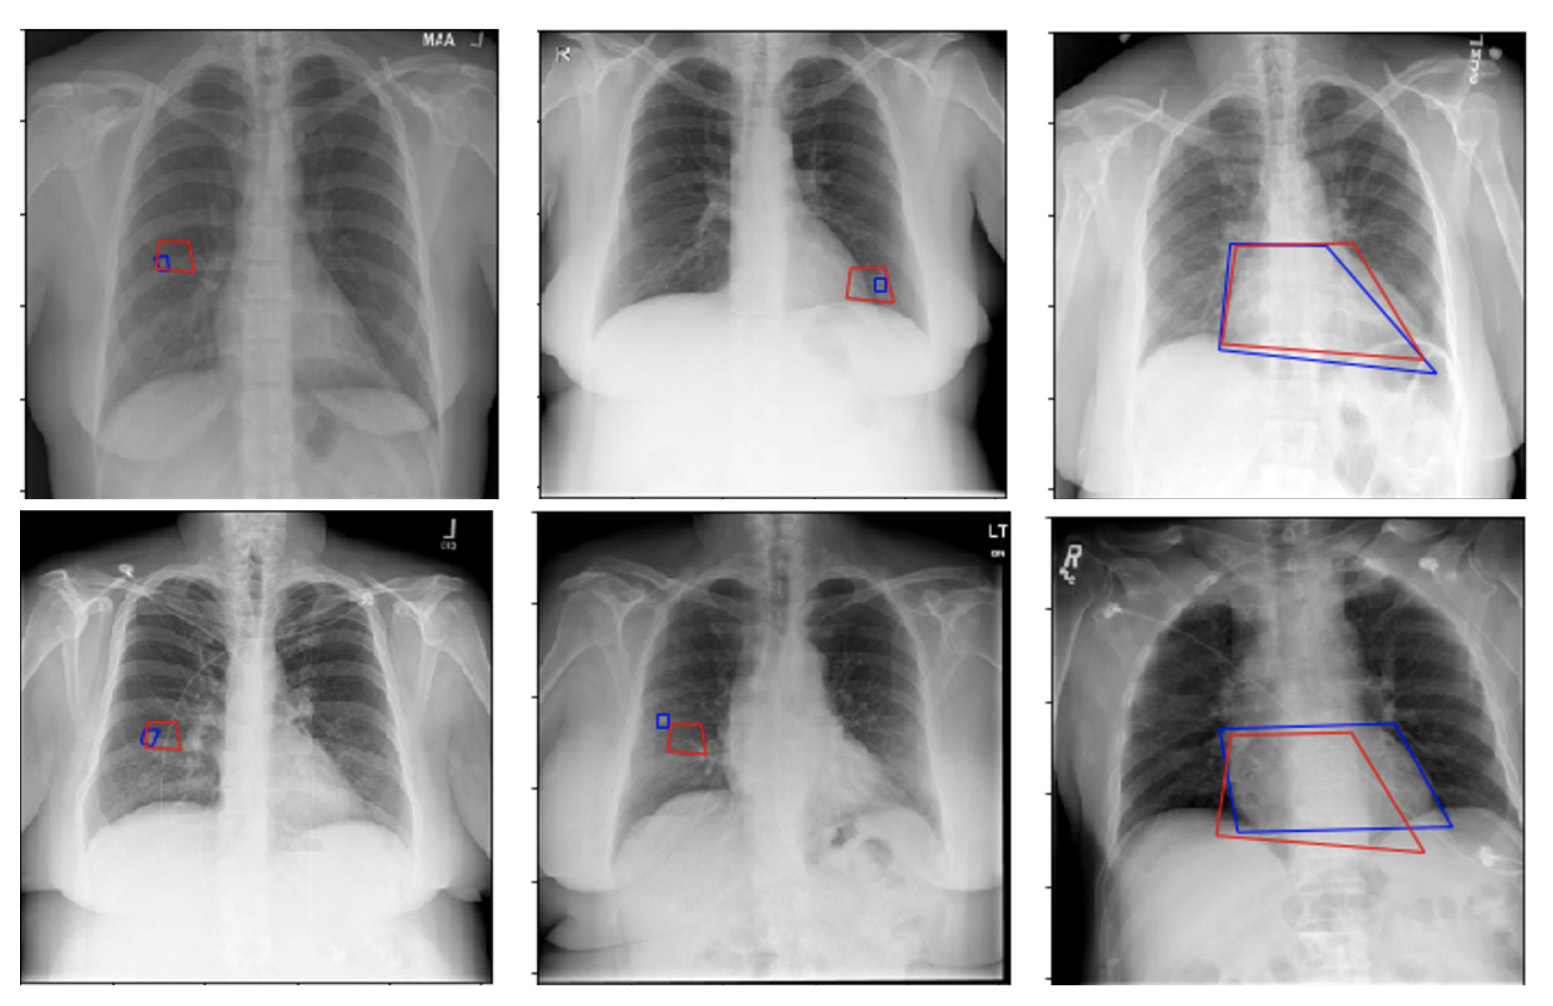

Medical image analysis

We make therapeutic picture examination programming for emergency clinic and practices around the world. In social insurance, computer vision PC vision is utilized as a feature of PC supported analysis programming helping specialists to identify anomalous signs in both 3D and plain pictures and recordings. While not having the capacity to supplant human clinicians, PC vision applications can turn into their dependable aides, bringing up regions worth exceptional consideration and in this manner decreasing human blunder in radiology.computer vision

• X-ray